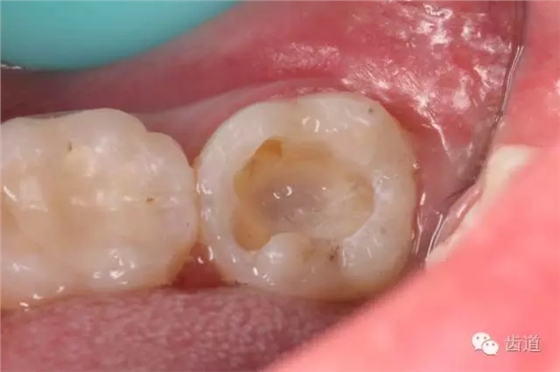

4. 初步開髓

5. Endo-Z揭全髓室頂

6. 可見髓腔內(nèi)壞死牙髓組織,無滲出